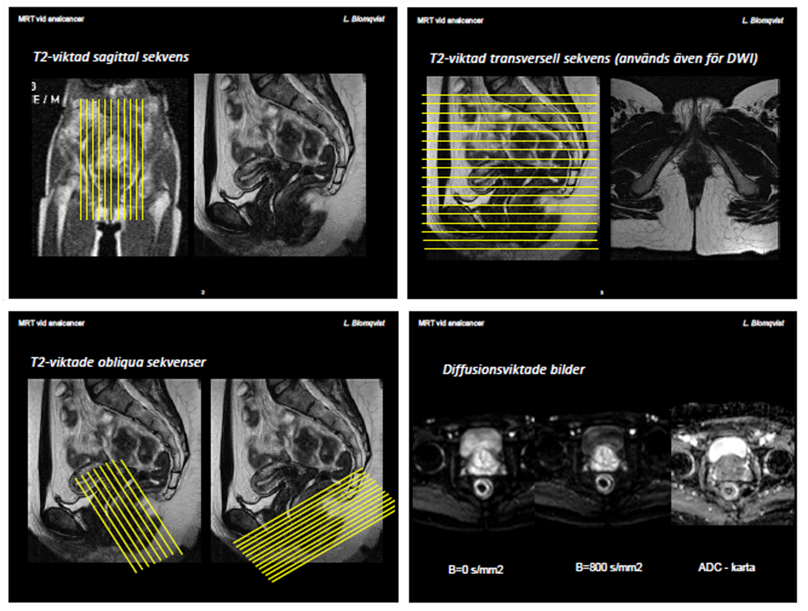

Vid biopsiverifierad analcancer görs en MRT lilla bäckenet för att kartlägga lokal tumörutbredning. Principerna för innehållet i MRT-undersökningen vad avser pulssekvensinnehåll är desamma som vid rektalcancer (figur 4). Viktigt är att hela analkanalen inkluderas med god marginal, både transversella, sagitella och vinklade sekvenser. MRT-undersökningen för kartläggning av lokal tumörutbredning bör beskrivas med utgångspunkt i TNM-klassifikationen av analcancer (tabell 1), vilken skiljer sig från TNM-klassifikationen vid rektalcancer.

Figur 4. MRT vid analcancer. Vinklingar och sekvenser.

Diffusionsviktad sekvens (DWI) används bäst för tumörer som är svårbedömda på de ordinarie T2-viktade sekvenserna och för detektion av små analtumörer. Lämpligen vinklas DWI sekvensen perpendikulärt mot analkanalens längsaxel, med 3–4 mm snitt-tjocklek och hög upplösning. Användning av b-värde 50–100 och 800–1000 för beräkning av ADC-map är att föredra. Ett alternativ vid svårbedömda fall kan vara en kontrastserie med högupplöst 3D T1-viktat gradienteko med fettsuppression som också kan bidra till bättre avgränsning av analtumören, då patologisk uppladdning ofta ses i dessa tumörer.